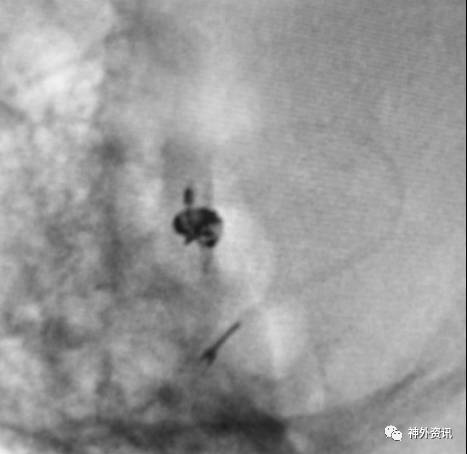

微导管成袢技巧

适用于:

(1)颈内动脉-眼动脉段的Carotid Cave动脉瘤

(2)大脑前动脉A1起始段的偏下方指向动脉瘤

(3)其他载瘤动脉近心端走行方向与动脉瘤指向之间大于90度的微导管到位

注意事项:

(1)上述动脉瘤指向的成角过大,即使使用微导丝进入动脉瘤囊内导引,微导管顺行到位也难以实现

(2)成袢的微导管常常弹跳进入动脉瘤囊内,有动脉瘤破裂风险

塑型要点:

(1)基于载瘤动脉走向与动脉瘤指向的微导管塑型,并适当增加微导管头端的直行长度,有助于成袢和微导管稳定性

(2)可利用颈内动脉分叉或大脑中动脉M1分叉进行微导管成袢

病例一

眼动脉动脉瘤,支架完全释放后,微导管成袢逆行到位